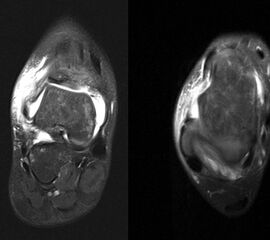

Typische Begleitverletzungen der Sprunggelenkdistorsion sind Luxationen der Peronealsehnen, Rupturen der Peronealsehnen sowie Verletzungen des unteren Sprunggelenks, der Syndesmose und des Calcaneocuboidalgelenks. Bei Grad III Verletzungen finden sich in über 80% der Fälle Schäden des Nervus peronaeus und des Nervus tibialis 17. Direkt nach dem Trauma ist aufgrund von Schmerzen und Schwellungen die Aussagekraft der klinischen Untersuchung oft eingeschränkt. Die größte Reliabilität und Spezifität bietet die klinische Untersuchung 4-7 Tage nach der Verletzung 18. Besteht nach 4-7 Tagen der klinische Verdacht auf eine Begleitverletzung, bzw. findet sich ein inadäquat hohes Schmerzniveau, lassen sich die meisten Pathologien mit einer MRT Untersuchung des Rückfusses umfassend beurteilen (Szeimies 2014).

Schnittbildverfahren sind immer dann indiziert, wenn der Verdacht auf Begleitverletzungen besteht, das Schmerzniveau inadäquat hoch ist, oder die akuten Beschwerden innerhalb einer Woche nicht weitgehend abgeklungen sind 31 (Abb. 4-6).